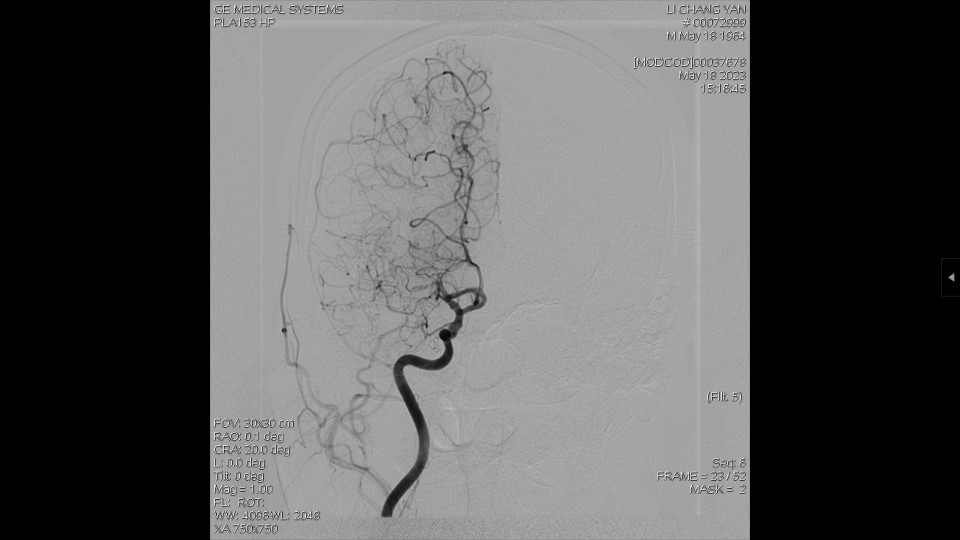

DSA显示:右侧MCA闭塞,依靠颅底软膜支、大脑前动脉代偿。